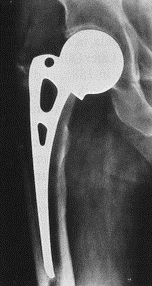

股骨柄的种类

Khanuja按几何形学分类:

- 1.单楔形

- 2.双楔形

- 3A,锥形圆柄

- 3B,锥形纵槽柄

- 3C,锥-矩形柄

- 4,全涂层柱形柄

- 5,组合式假体

- 6,曲形解剖设计